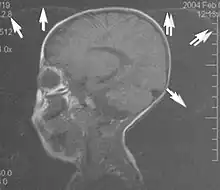

Flow can manifest as either an altered intravascular signal (flow enhancement or flow-related signal loss), or as flow-related artifacts (ghost images or spatial misregistration). Flow enhancement, also known as inflow effect, is caused by fully magnetised protons entering the imaged slice while the stationary protons have not fully regained their magnetization.[1] The fully magnetized protons yield a high signal in comparison with the rest of the surroundings. High velocity flow causes the protons entering the image to be removed from it by the time the 180-degree pulse is administered. The effect is that these protons do not contribute to the echo and are registered as a signal void or flow-related signal loss (Fig. 2).[1] Spatial misregistration manifests as displacement of an intravascular signal owing to position encoding of a voxel in the phase direction preceding frequency encoding by time TE/2.The intensity of the artifact is dependent on the signal intensity from the vessel, and is less apparent with increased TE.[1]